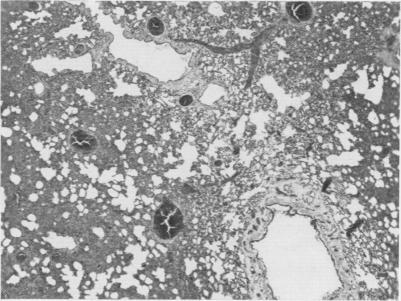

Endotoxin shock. A manifestation of intravascular coagulation.

Ann Surg. 1961 Nov;154(5):791-802. doi: 10.1097/00000658-196111000-00003.